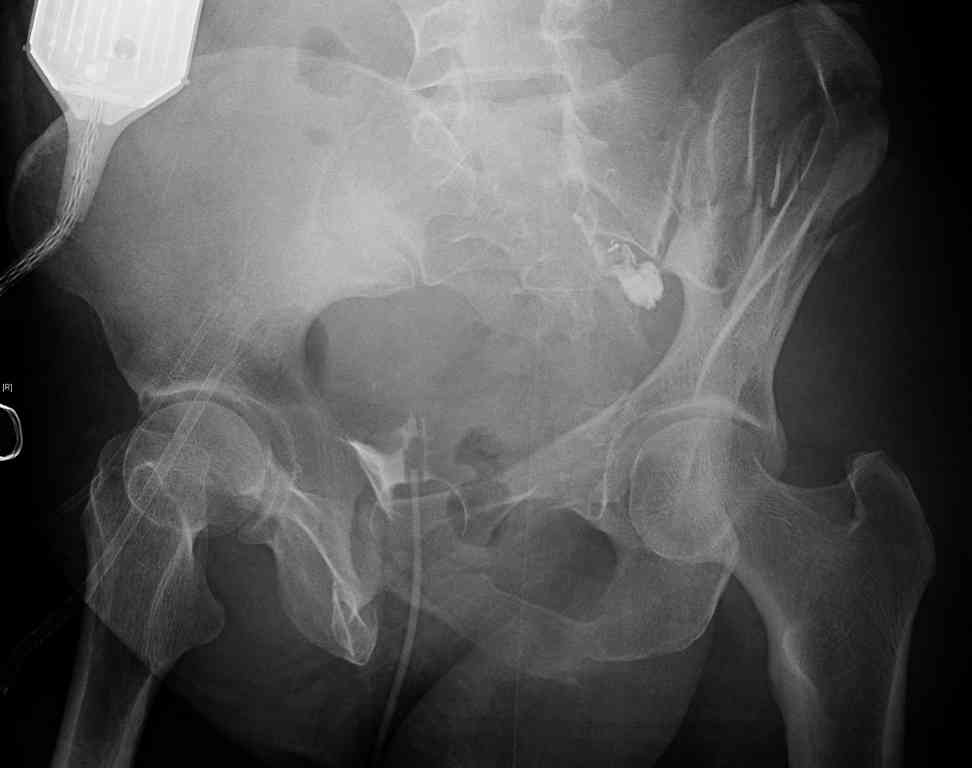

comminuted crescent fx

40 ish female ejected from car. Unstable, DPL negative, went to angio and had her pelvic bleeds embolized after many units of blood. GCS 6, floating elbow, clavicle, bothbones, etc.

My standard approach to this pelvis would be posterior, reduce/lag/plate thecrest, reduce/plate the caudal extent on the posterior crest and 1-2 lags back to front. In this case, the crest comminution seems to make plating all the way to the ASIS useless, as the plate would be on free floating fragments. Would plating the posterior extent of the fracture to secure the reduction at the SI joint and 2 screws back to front be sufficient fixation? Would anyone do a perc reduction and perc back to front screws, and would that be sufficient if the SI joint could be reduced (although I don't see how this could be accurately reduced closed). Would an ilioninguinal with a pelvic brim plate and posterior column screws be a better approach, although reducing the SI would be more indirect and less accurate?

It's a comminuted iliac fracture involving the GS notch and all that

implies...use the lateral interval of an ilioinguinal, sequentially reduce,

and fix...if you want to, you can attach the dominant unstable fragment to

both the stable posterior iliac fragment and also to the anterolateral portion of the sacrum using plates...if you choose to anchor to both, the implants get congested on the iliac side of the SI joint so be precise with contouring and such applications...perhaps and based on the images shown, an iliosacral screw would only augment the construct if applied to the second sacral segment (but this is difficult to assess on the images shown). The crest components can be held securely with screws and/or peripheral plating.

I always manage these percutaneously. The basic idea is to peg the AIIS fragment to the crescent frag still attached to the sacrum.

But the reported results of open treatment are very good, so your plan of ORIF should yield acceptable results.